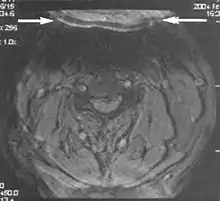

A wrap-around artifact also known as an aliasing artifact, is a result of mismapping of anatomy that lies outside the field of view but within the slice volume.[4] The selected field of view is smaller than the size of the imaged object. The anatomy is usually displaced to the opposite side of the image (Figs 6 and 7). It can be caused by non-linear gradients or by undersampling of the frequencies contained within the return signal.[1] The sampling rate must be twice the maximal frequency that occurs in the object (Nyquist sampling limit). If not, the Fourier transform will assign very low values to the frequency signals greater than the Nyquist limit. These frequencies will then ‘wrap around’ to the opposite side of the image, masquerading as low-frequency signals. In the frequency encode direction a filter can be applied to the acquired signal to eliminate frequencies greater than the Nyquist frequency. In the phase encode direction, artifacts can be reduced by an increasing number of phase encode steps (increased image time). For correction, a larger field of view may be chosen.[1]